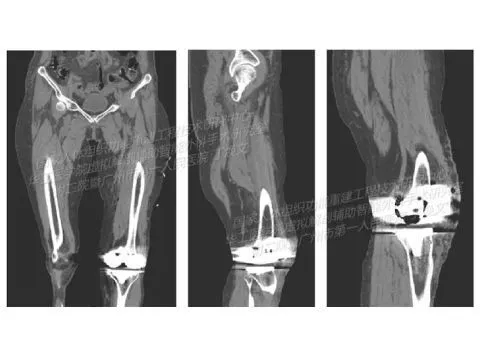

Лечение остеоартрита коленного сустава у пациентки 63 лет (проект Национального проектно-исследовательского центра реконструкции тканей и Первой народной больницы Гуанчжоу, Китай)

• Эндопротезирование коленного сустава с применением цифровых технологий и 3D‑печати металлом

• Используя 3D‑модель коленного сустава на основе КТ и SLM‑технологию, специалисты спроектировали оптимальное положение хирургического шаблона

• Для быстрого создания персонализированного хирургического шаблона для эндопротезирования сустава использован эффективный и безопасный SLM‑принтер HBD‑150

• Достигнута высокая степень прилегания между шаблоном и коленным суставом